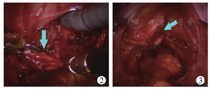

打开盆底腹膜,沿双侧输精管寻找前列腺小囊。由前列腺小囊的顶端向盆底方向游离前列腺小囊,避免损伤直肠和输尿管(图2)。游离前列腺小囊至尿道。于前列腺小囊前壁远端纵向切开囊壁,明确前列腺小囊汇入尿道的位置,避免尿道损伤。于双侧输精管汇入前列腺小囊顶端的水平切断前列腺小囊。于靠近尿道处切断前列腺小囊颈部。移除中间段的前列腺小囊组织,用6-0 Vicryl将连着双侧输精管的前列腺小囊壁与尿道端的前列小囊残壁进行吻合(图3)。在盆底放置一根引流导管。

注:箭头所指为将双侧输精管吻合至后尿道上处